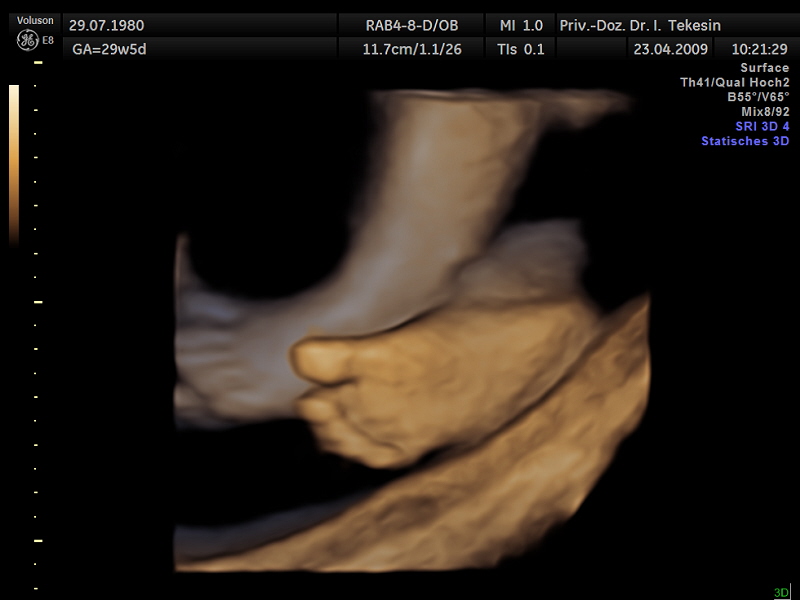

3D-/4D-Ultraschall (optional)

Immer mehr werdende Eltern interessieren sich für die faszinierenden Bilder, die dieses Verfahren liefert. Die plastische, dreidimensionale Darstellung der Oberfläche des Gesichts und anderer Körperregionen wird durch spezielle Bildrekonstruktion in schnellen Rechnern erreicht. Auch einzelne innere Organe oder „Gefäßbäume“ können von allen Seiten betrachtet werden. Viele dünne Schnittebenen (2D) werden zu einer gemeinsamen 3D-Sichtweise im Computer des Ultraschallgerätes zusammengeführt. Unter einem 4D-Ultraschall versteht man darüber hinaus eine 3D-Ultraschalluntersuchung unter Echtzeitbedingungen. Anstatt nur statische Bilder anzuzeigen, erfasst ein 4D-Ultraschall die Bewegungen des Kindes, weshalb er auch als „Live-3D-Ultraschall“ bezeichnet wird.

Diese Vorgehensweise ermöglicht äußerst realistische Bilder, bei denen sogar Gestik und Mimik des Kindes in bewegten Sequenzen festgehalten werden können. Die Untersuchung kann wie auch der normale Ultraschall während des gesamten Schwangerschaftszeitraums durchgeführt werden. Möchte man das Ungeborene komplett sehen, wird die 12. bis 16. Schwangerschaftswoche empfohlen, die Zeit zwischen der 28. und 33. Schwangerschaftswoche eignet sich besonders zur präzisen Darstellung einzelner Körperteile

Wir sehen in diesem modernen Verfahren in erster Linie eine ergänzende Maßnahme bei speziellen Fragestellungen bezüglich Herz, Gehirn oder Skelett und vor allem bei Verdacht auf eine fetale Besonderheit.

Kind in der 28. Woche (3D-Darstellung)

Fünf Finger (3D-Darstellung)

Ein Fuß (3D-Darstellung)

Ein freches Kind in der 38. Woche (3D-Darstellung)

Ohr und Haare in der 34. Woche (3D-Darstellung)